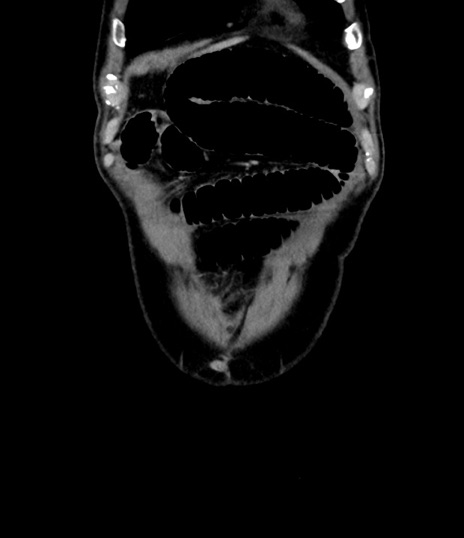

症例8(冠状断像)

【症例】 60歳代男性

【主訴】 黒色吐物

【現病歴】 4日前から嘔気自覚、2日前の朝食後にも嘔気あり、自分で手で嘔吐反射起こし嘔吐したところ血が混ざっていたため受診。

【既往歴】 5年前汎発性腹膜炎を伴う急性虫垂炎で手術、高血圧、前立腺肥大症、高脂血症

【身体所見】 腹部正中に手術癩痕あり 腹部平坦・軟圧痛なし膨満感あり

【データ】WBC 8400、CRP 4.54